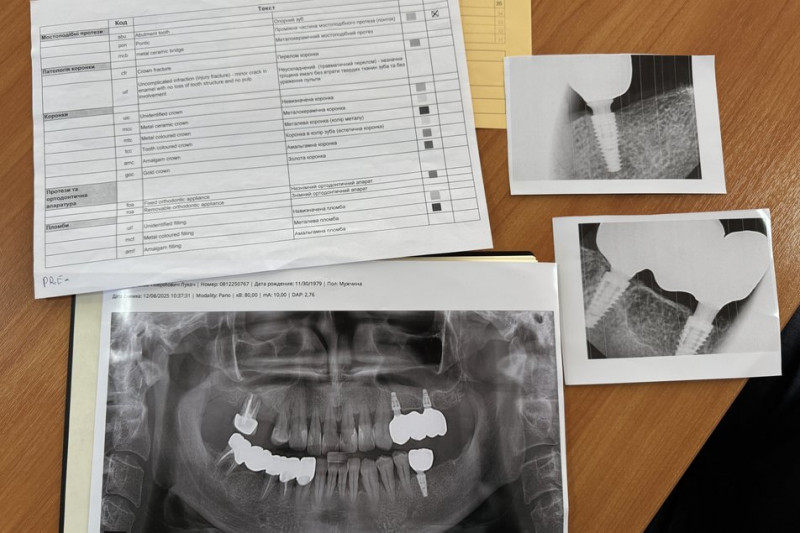

Знімки роблять під час навчального курсу "Особливості комплексної одонтологічної експертизи військовослужбовців", який проводять для судмедекспертів на стоматологічному факультеті УжНУ. Долучився до такого курсу і працівник Закарпатського бюро судово-медичної експертизи Мирослав Лукач.

"На початку курсу кожен із нас зробив ортопантофотограму або як їх у народі називають панорамні рентгенограми нижньої щелепи. І, відповідно до таблиці міжнародної, де є всі позначення, тут описано англійською мовою перші три букви, а далі йде український коментар. Згідно з цією таблицею ми складували такий бланк анте-мортем (прижиттєвий — ред.). Тобто дентальний статус зниклого безвісти", — розказав працівник Закарпатського бюро судово-медичної експертизи.

Знімки щелепи. Суспільне Ужгород/Сергій Чернишов"Це — рентгенологічний апарат, який може створювати як панорамний знімок 2D, так і конусно-променевий зріз для нижньої й верхньої щелепи для можливості в подальшому тлумачити стоматологічний статус. Сучасні можливості дентальної рентгенології, яка є в стоматологічній галузі, дозволяють мати чіткі зразки індивідуалізовані, які не повторюються більше ніде. І це дає можливість потім нам ідентифікувати ту чи іншу людину", — додав в.о. директора науково-навчального інституту стоматології та лабораторної медицини УжНУ Євген Костенко.